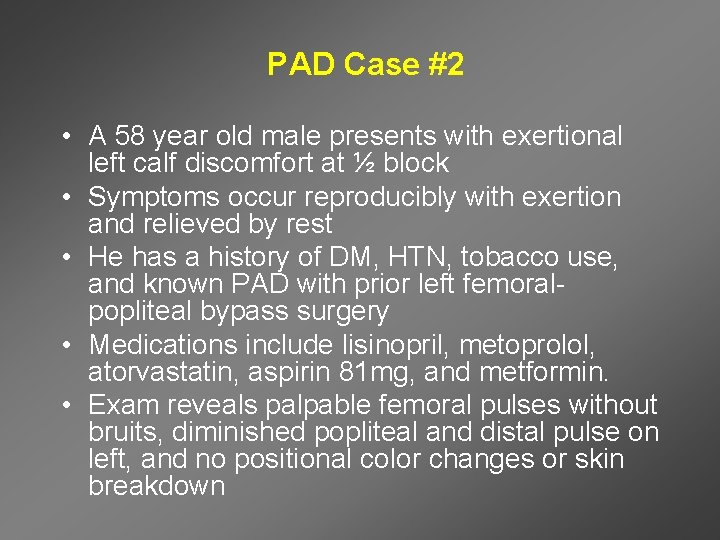

PAD Case #2 • A 58 year old male presents with exertional left calf discomfort at ½ block • Symptoms occur reproducibly with exertion and relieved by rest • He has a history of DM, HTN, tobacco use, and known PAD with prior left femoralpopliteal bypass surgery • Medications include lisinopril, metoprolol, atorvastatin, aspirin 81 mg, and metformin. • Exam reveals palpable femoral pulses without bruits, diminished popliteal and distal pulse on left, and no positional color changes or skin breakdown